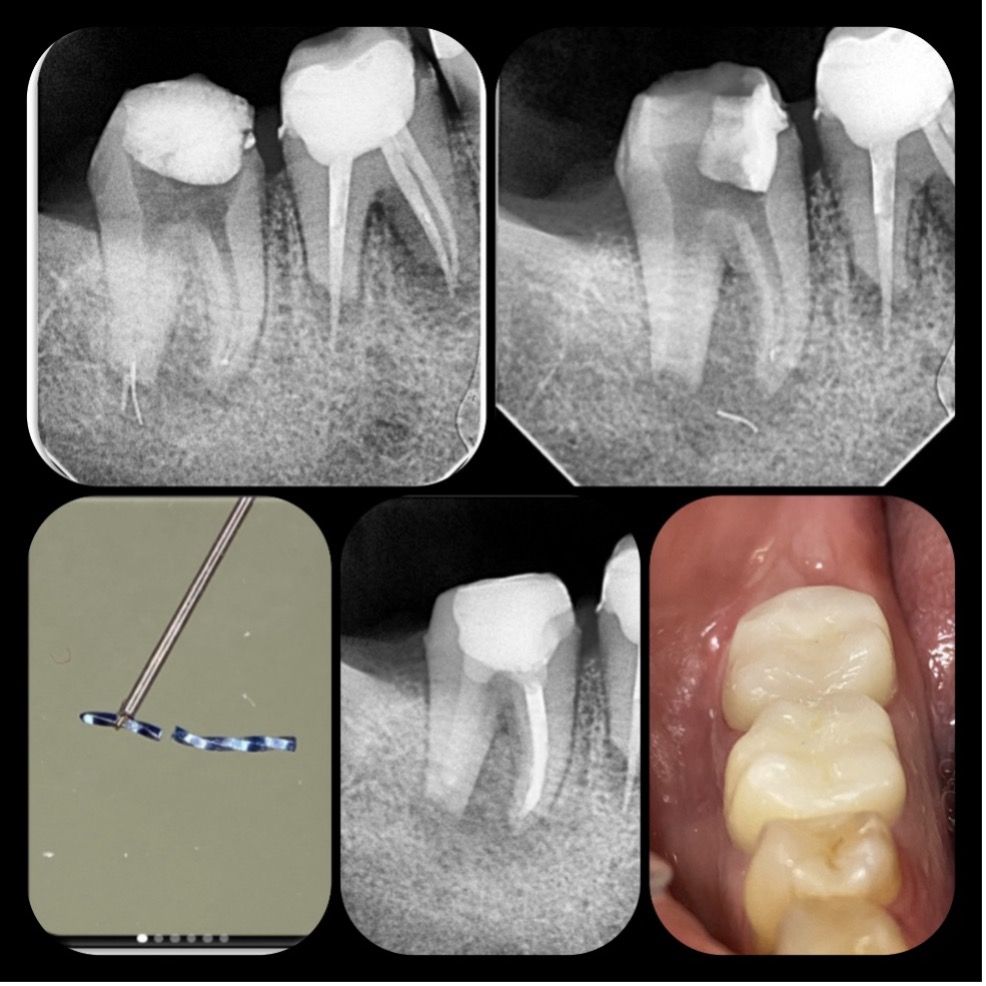

29 yaşındaki sağlıklı erkek hasta kök kanalındaki kırık eğe nedeni ile kliniğimize başvurdu. Yapılan radyografik muayenede distal kanalda apikalden taşkın guta ve kırık alet olduğu tespit edildi (RESİM 1).

RESİM 1: Apikalden taşkın eğe ve guta